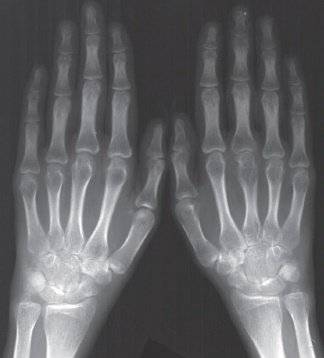

Четвертая стадия

Четвертая степень заболевания характеризуется появление необратимых изменений в пораженном суставе, которые отчетливо видны по данным рентгенографии. Изменения эти столь выражены, что их можно заменить даже без КТ или рентгена: просто используя УЗИ.

- наличие множественных эрозивных образований, кистозных элементов;

- фиксируется атрофия мышечной ткани вокруг пораженного хряща;

- существенно усиливаются проявления остеопороза;

- просвет в хрящевой щели едва различим даже по данным компьютерной томографии;

- помимо подвывихов в пораженном суставе часто фиксируются вывихи;

- отчетливо наблюдается деформация ткани, изъяны на хрящевой поверхности;

- у большинства пациентов можно заметить отложения солей кальция (из-за кальцификации отдельных элементов мягких тканей, которые локализуются вокруг пораженного сустава).

Это заключительный этап: четвертая стадия характеризуется инвалидностью. Лечить ее нечем, консервативные методы часто неэффективны даже в качестве симптоматической терапии. Единственный выход – оперативное вмешательство, сопряженное с отдельными рисками.